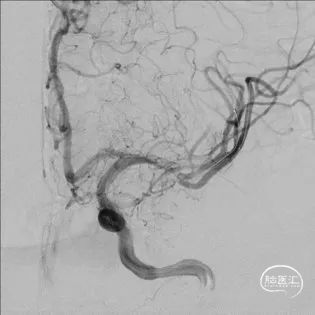

DSA

重要影像结论:左大脑中动脉M1末端重度狭窄。

导引导管到位,导丝通过病变

扩张后造影